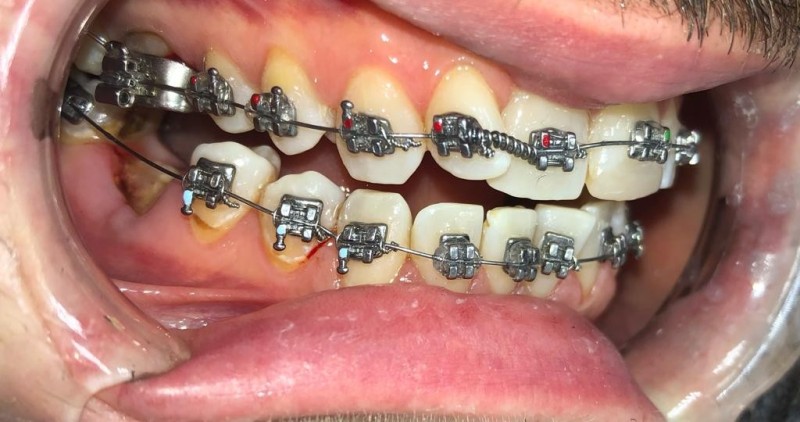

Установка брекетов Damon

Фото на этапе лечения через 4 месяца, брекеты Damon Q

Доктор: Жвания Нала Анзоровна